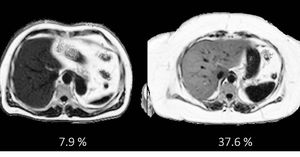

New study showed that 1 in 5 participants (5.000 the total number of participants) had fatty liver, demonstrating the scale of epidemic facing the UK population. Images were acquired at the dedicated UK Biobank imaging Centre at Cheadle (UK) using a Siemens 1.5T MAGNETOM Aera. http://journals.plos.org/plosone/article?id=10.1371/journal.pone.0172921 Article's title: Characterisation of liver fat in the UK Biobank cohort #MRI #Quantitative_MRI #Q_MRI #fatty_liver_disease